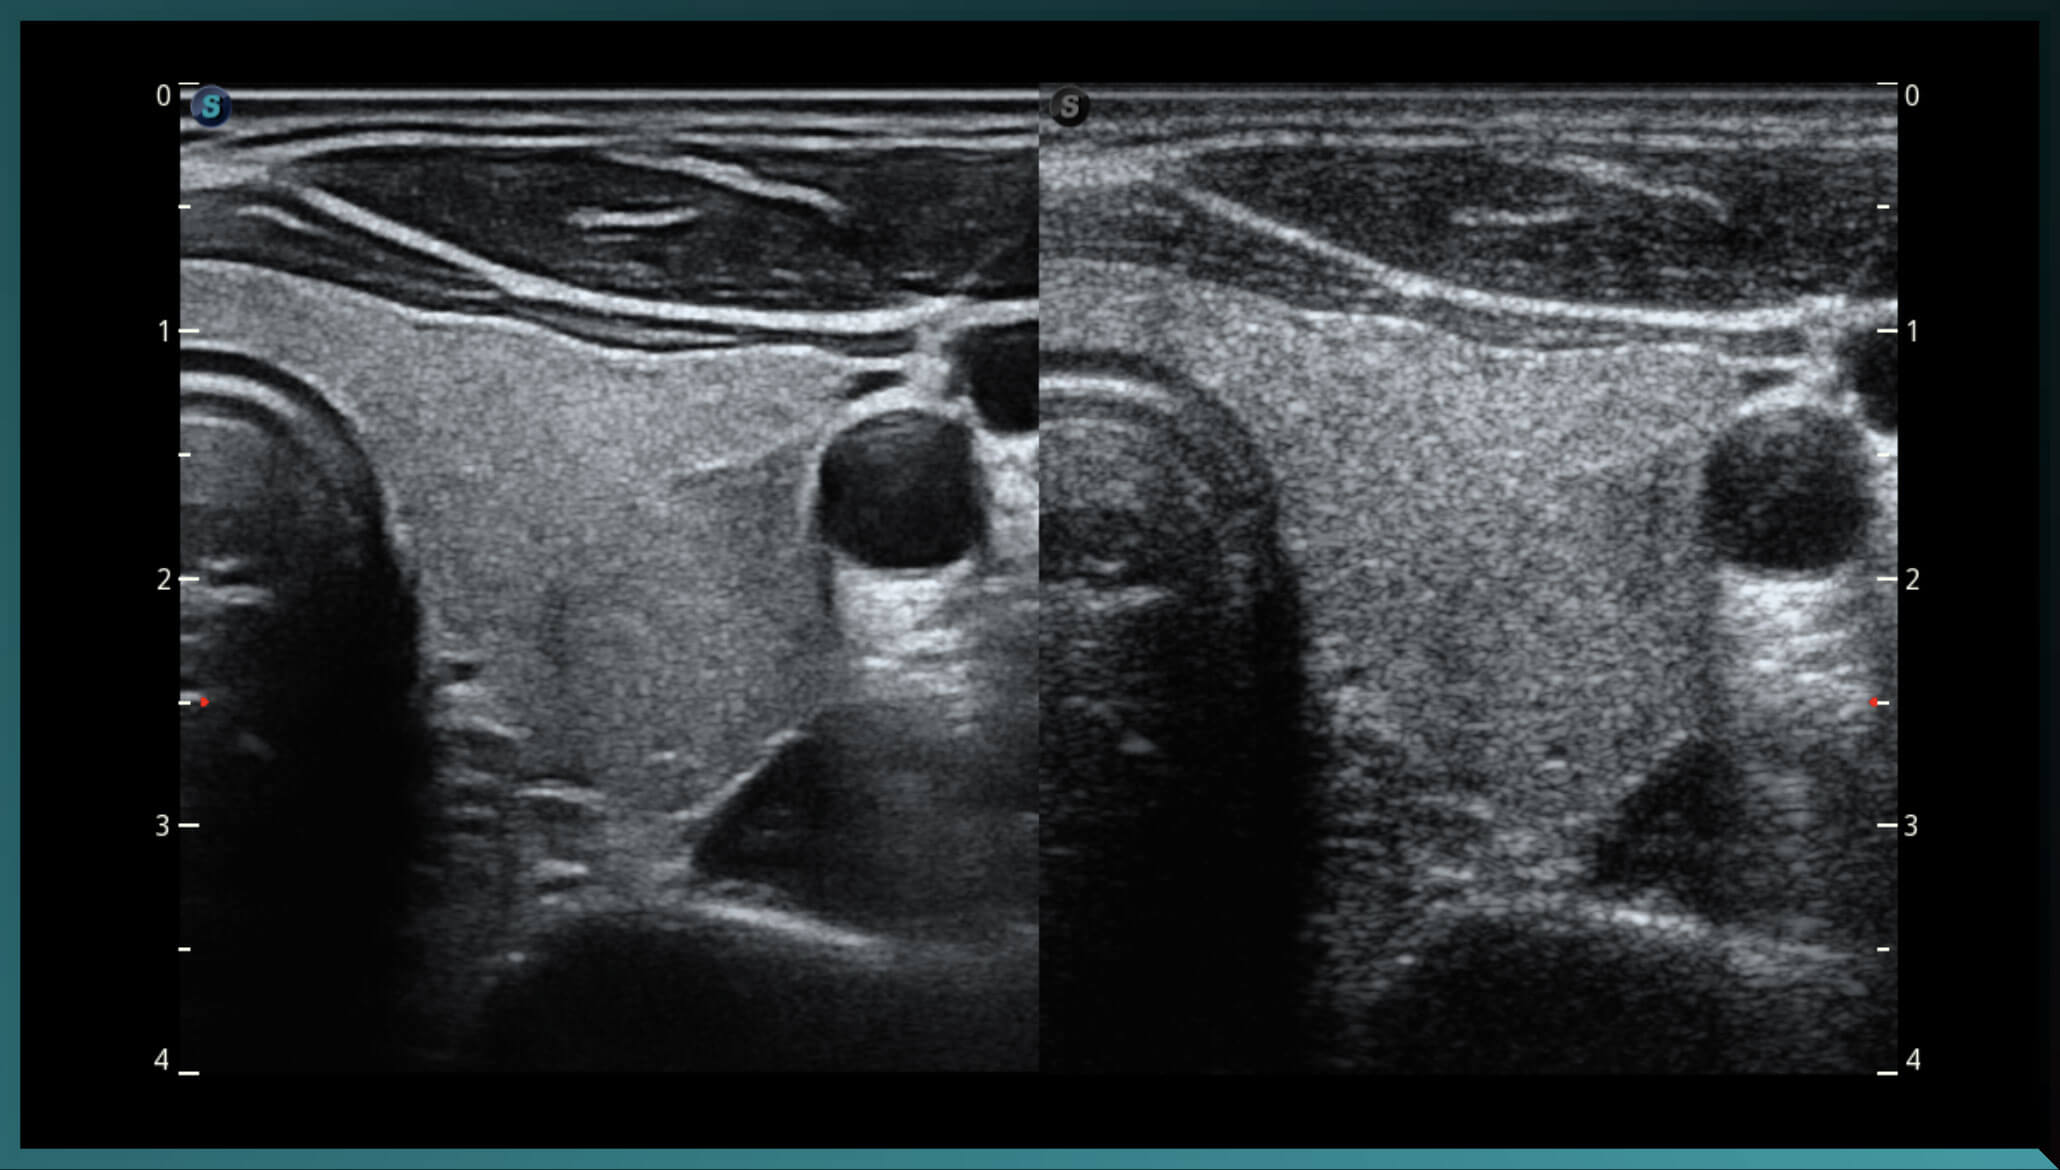

Micro F ( siêu âm vi mạch)

Micro F cung cấp một phương pháp cải tiến để mở rộng phạm vi dòng chảy có thể nhìn thấy trong siêu âm, đặc biệt là để hình dung huyết động của các mạch máu nhỏ. Mang lại sự tự tin chẩn đoán cao hơn để đánh giá các tổn thương và khối u.